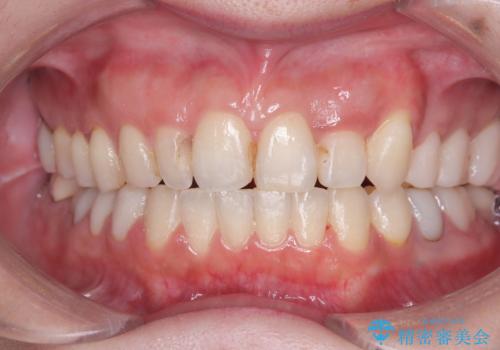

前歯の突出を防ぎながらガタつきを解消。上下左右4番抜歯による審美ワイヤー矯正

担当医 河口智英